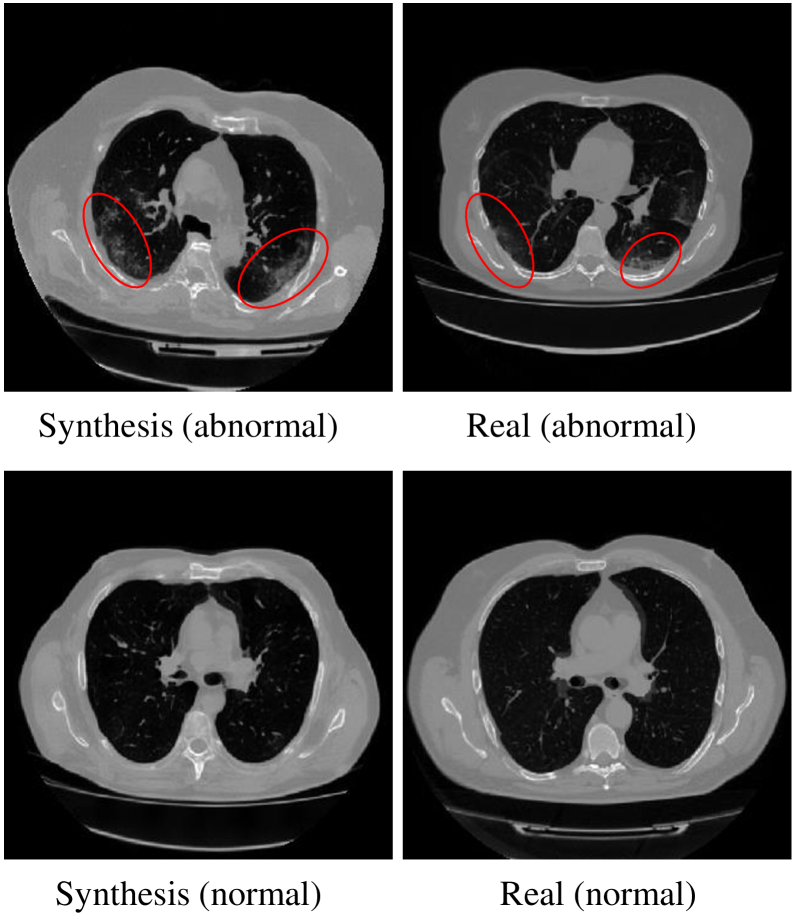

4.5.4 Data Augmentation for Classification

In this experiment, we demonstrate the feasibility of leveraging the synthesized samples from generative model to augment the training dataset for a classification task. Different from the three downstream tasks above, in this task, we do not use the ControlNet but fine-tune our generative model on the MosMedData [63], which consists of 1,110 studies, including both those with COVID-19 related findings and those without. The experiment was designed as follows: first, we fine-tuned our model on this dataset with minor modifications, using two class labels: for studies with COVID-19 related findings (abnormal) and for studies without COVID-19 findings (normal). Next, we used the trained model to generate new images with corresponding class labels (200 images for each of the two classes). Finally, we combined the original training dataset with the synthetic images to train a binary-class classifier as the augmented classifier, and used the original dataset without synthetic images to train another binary-class classifier as the baseline classifier. We then evaluated the performance of both classifiers on the test set. The dataset was split into training, validation, and test sets, with the test set containing containing 120 images. The model and classifiers were trained and evaluated on a single NVIDIA A100 GPU with 80GB of memory. We report the quantitative results in Tab. 11. Additionally, we show some synthetic images with and without COVID-19 related findings in Fig. 13. It can be observed that our proposed method generates realistic normal and abnormal lung CT images. Moreover, the classifier trained with synthetic augmented data outperforms the baseline model, which was trained only on real images from the training set.